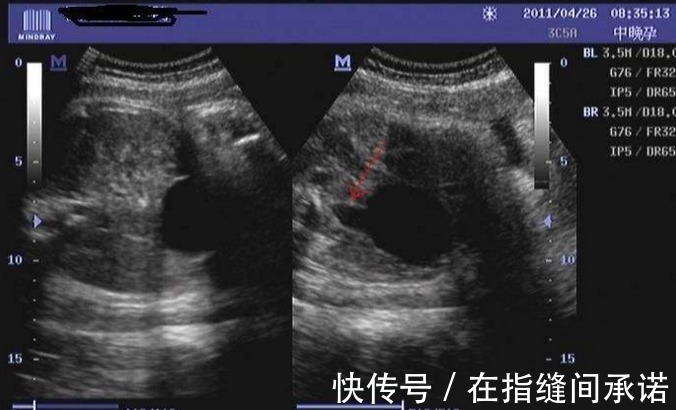

第三是反应灵敏胎儿的智力发育比较好的,反应也会比较灵敏。对于外界的感知能力会比较快,一点风吹草动,胎儿就激动地在孕妈肚子里手舞足蹈。反应灵敏,其实也表现在胎动。一般来说,孕妈妈在洗澡后,吃饭后,夜晚的时候,胎动会比较明显。还有的孕妈妈,在听某种音乐的时候,胎动比较明显。

有人做过一个实验,在孕期孕妈做B超的时候,把探头轻轻往肚子上一放,有的胎儿就会远离探头的位置,这样就属于灵敏机智的胎宝宝。他们在妈妈的肚子里会感觉到肚子外部力度有变化。但是他们对这种情况又不太熟悉,所以聪明的孩子出于保护自己的目的,会远离他们认为危险的地方。